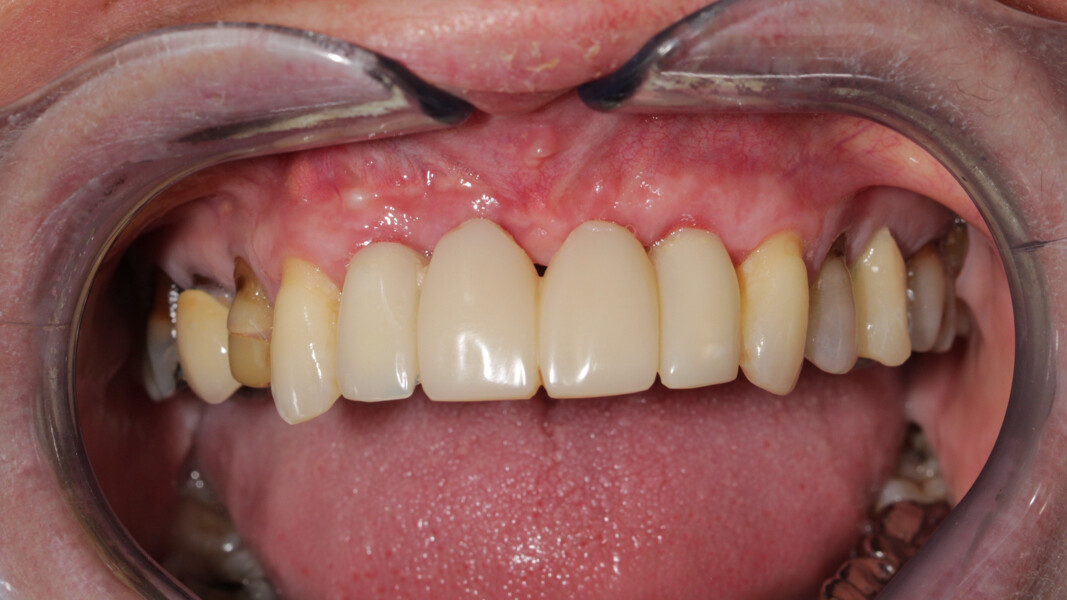

Le but du traitement est le remplacement des quatre incisives par un bridge implanto-porté de 12 à 22. Le plan de traitement mis en place est le suivant : extraction des deux incisives centrales et réalisation d’un bridge provisoire dento-porté fixe de 12 à 22 ; trois mois de temporisation permettant la cicatrisation des tissus mous, ainsi que la mise en oeuvre de la thérapeutique parodontale (Fig. 27) ; extraction de 12, 22 et 18, mise en place des implants, reconstruction de la crête (avec les racines extraites), mise en place d’un bridge provisoire fixe de 12 à 22, transvissé sur les deux implants.

Les sutures sont retirées à 15 jours. Un contrôle de la bonne ostéointégration des implants est réalisé à 2 mois postopératoire (Figs. 36 et 37). La réalisation de la prothèse d’usage par notre correspondant intervient à 9 mois postopératoire (Fig. 38).